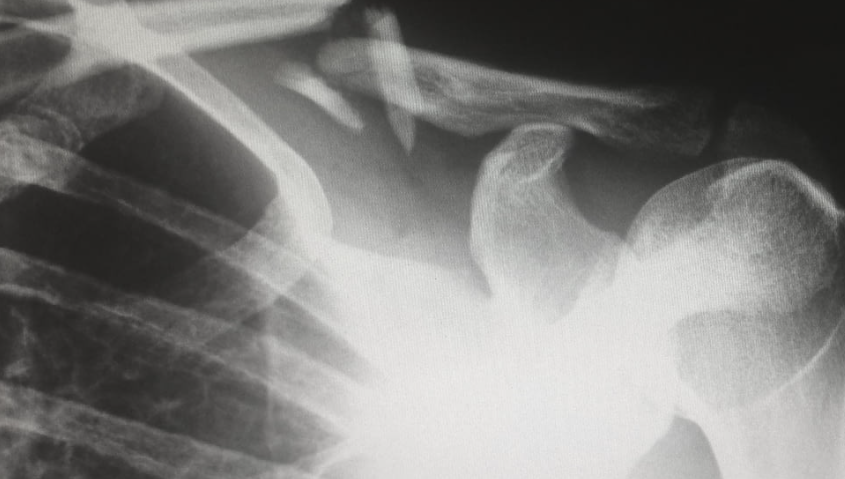

仅仅2年时间左右,人工关节、创伤、脊柱,一个接一个,骨科几乎成为集采最为彻底的高值耗材领域。

在7月11日发布的脊柱国采1号文中,根据手术类型、手术部位、入路方式等,囊括进了14套脊柱系统(详情见文末),相比征求意见稿,将脊柱用骨水泥单独列出,更符合市场情况。

有业内人士表示,这14套系统,几乎是“不留死角”,意味着所有脊柱产品都要被集采到!